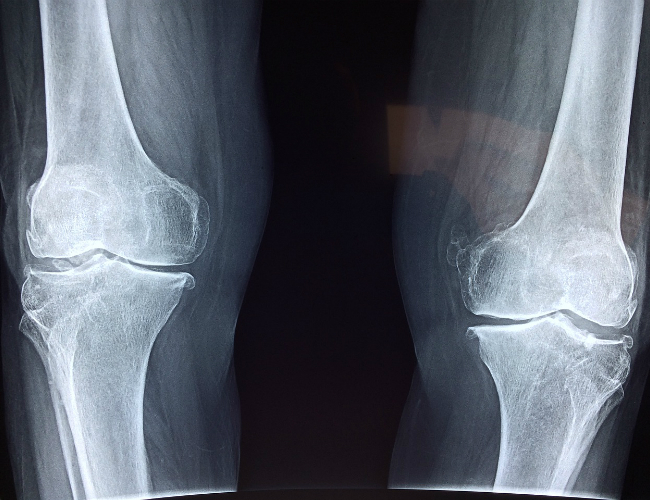

We aim to deliver the highest quality of service for our patients. In order to achieve this objective, we have gathered an extensive array of tools required to offer a fully comprehensive and enhanced standard of care. One of those key tools is our in-house X-ray technician who provides on-site X-ray imaging which allows us to determine the extent of an injury without having to send patients to a radiologist.

An X-ray (also referred to as a radiograph) is a type of medical imaging (radiology) that creates pictures of your bones and soft tissues, such as organs. To make these images, X-rays use safe amounts of radiation and send beams through the body. These beams are then absorbed in different amounts depending on the density of the material they pass through. The more solid or dense objects (such as bones) absorb radiation easily, making them appear bright white on the image. Soft tissues and less dense objects (such as organs) do not absorb radiation as easily, causing them to appear in shades of gray on an X-ray image.

The images enable providers to make immediate assessments, diagnose conditions, and plan treatments.